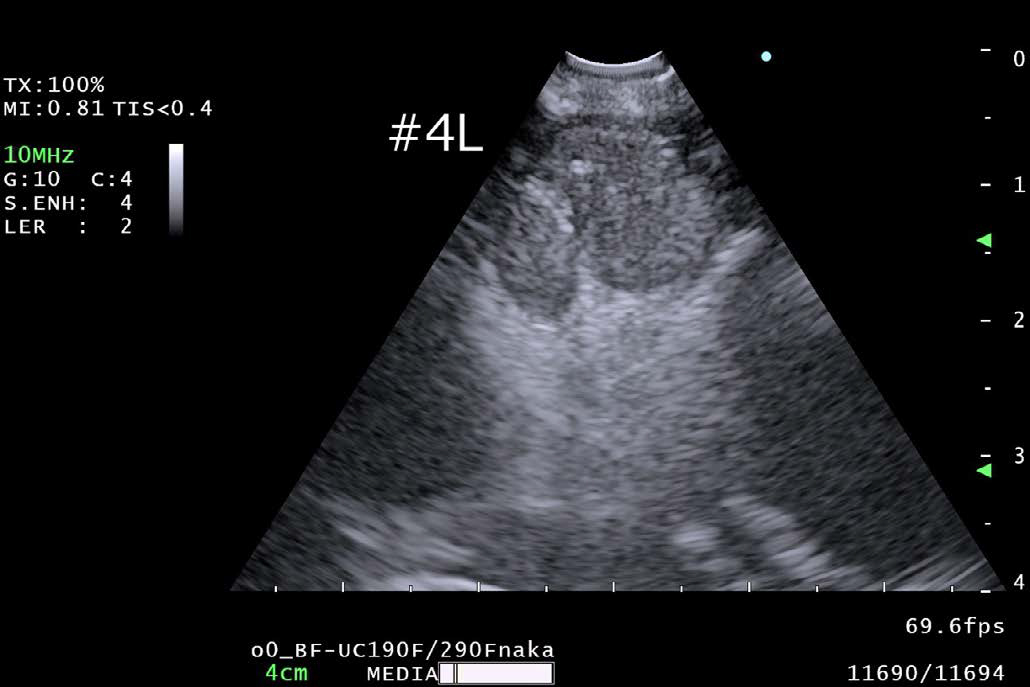

B モード

•  Bモード画像は、高画質化が実現されており、明瞭な超音波画像を得ることができる。全ての観測モードの基本であるBモード画像の画質が改善されたことで、EBUS検査全体の向上に寄与すると考える。従来機種(EU-ME2)と比較して、分解能・深達度ともに向上しており、各構造物の辺縁がよりはっきりと識別できるようになっただけでなく、リンパ節内部のエコー画像解像度が改善されたことで、リンパ節断面のテクスチャが感じられるようになった。

• 4L リンパ節観察